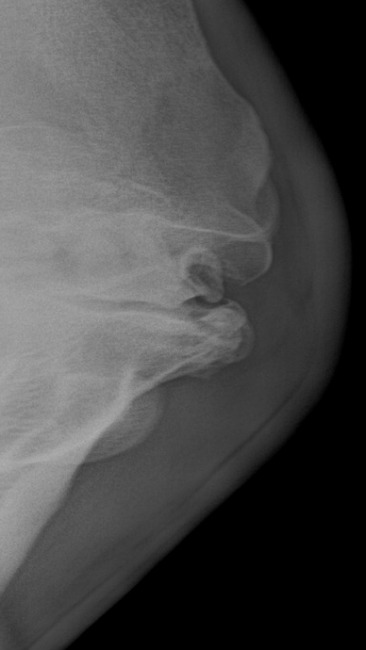

jest źle. Laluś miał wykonane zdjęcia RTG zarówno łopatki, jak i kopyt. Deformacja łopatki wymaga podawania leków, dodatkowo Laluś ma ochwat, a co za tym idzie przed nim wielomiesięczne leczenie, co wiąże się z dużymi kosztami.

Opis weterynaryjny: Obrzęk i deformacją prawej kończyny piersiowej w okolicy stawu ramiennego- badanie radiologiczne wykazało znaczne zmiany zwyrodnieniowe, deformację stawu barkowego

Zalecenia: Terapia przeciw bólowa i przeciw zapalna w celu ograniczenia bólu stawu barkowego . Werkowanie kopyt uwzględniając położenie kości kopytowej w puszce kopytowej najlepiej na sedacji

Stał u sąsiada, bez stada, dzień za dniem, miesiąc po miesiącu, zapadając się w samotność równie mocno jak w ból, bo Laluś ma ochwat, i wszystko wskazuje na to, że ma też wybity albo zwichnięty bark, z którym nikt nic nigdy nie zrobił.